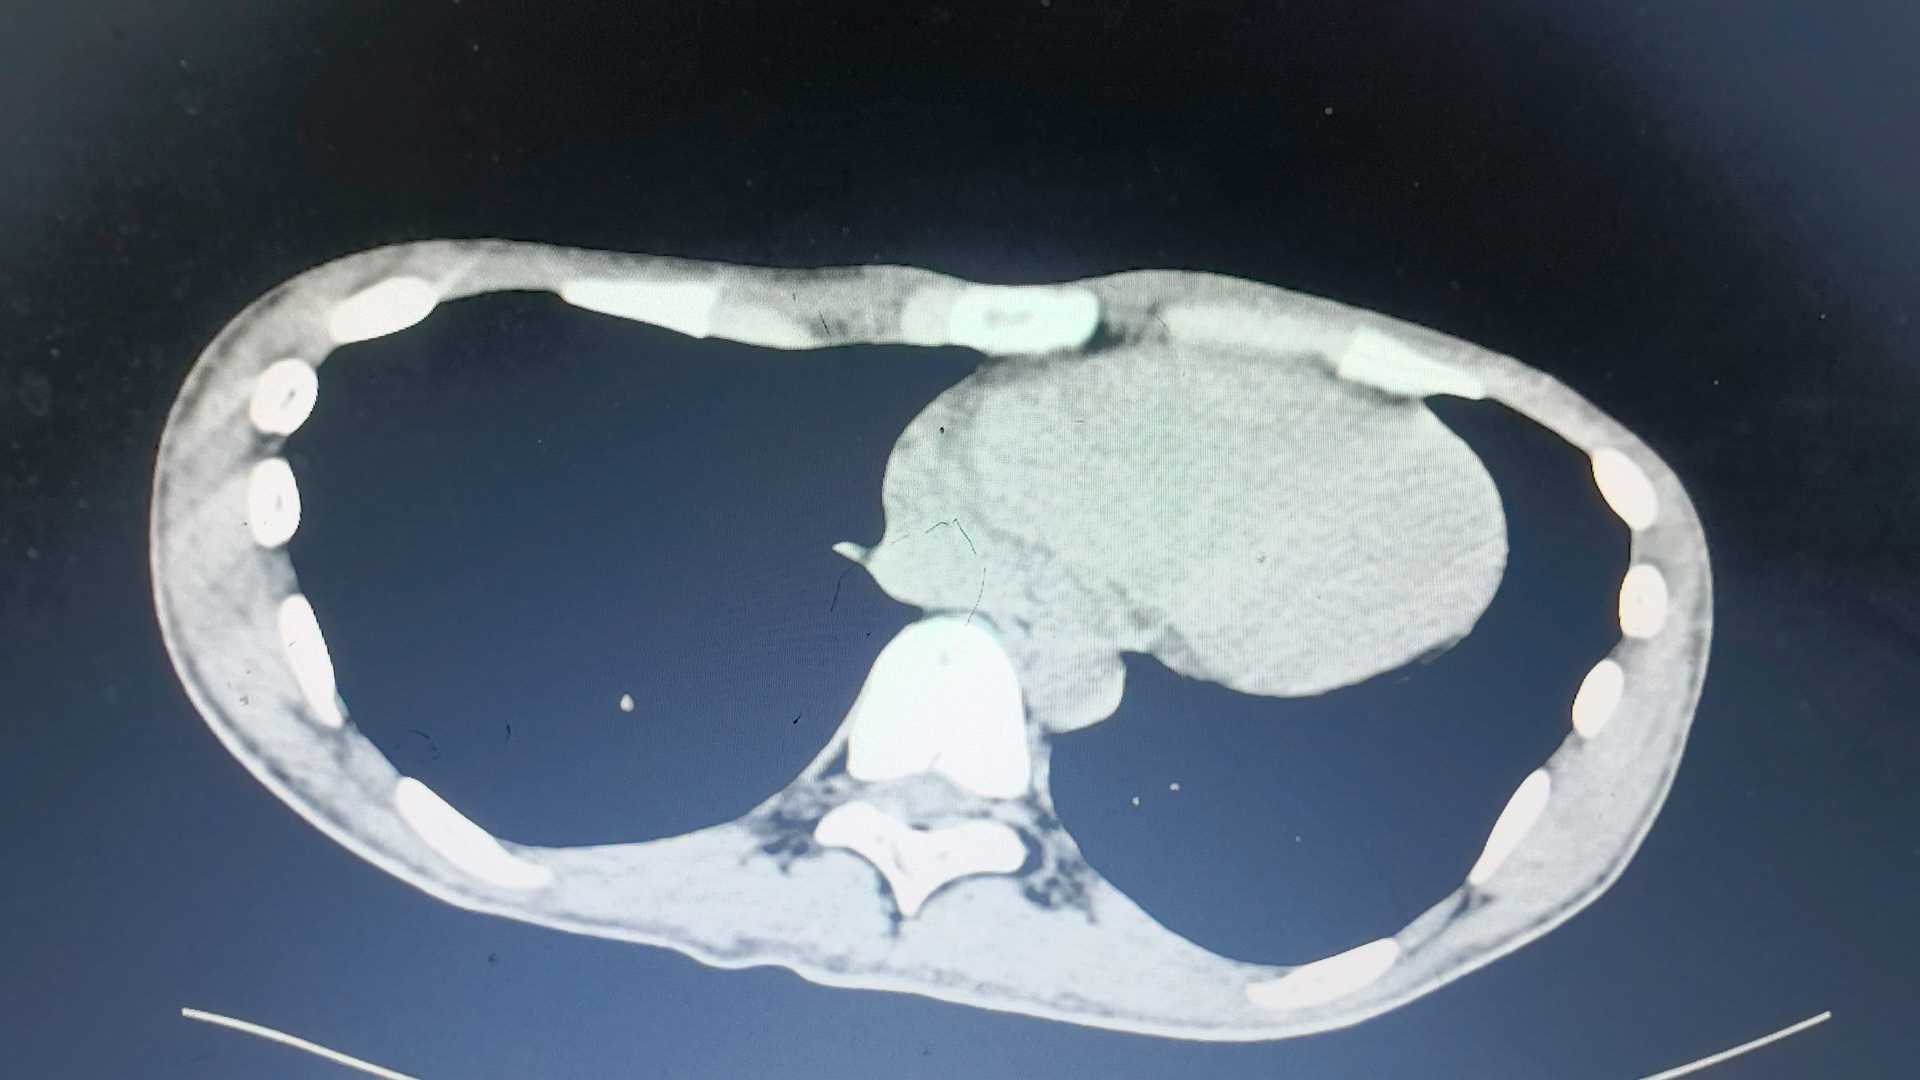

ct,

(大家可以通过胸腹腔轮廓了解患者体型)

在ct结果未实际出具时,自行阅片:腹腔有渗出,盆腔有积液,阑尾有粪石,未见游离气体影,肠道结构紊乱,肠内容物较多。

①患者腹痛门诊已经例行腹部ct,虽结果未出具,但和ct室老师沟通,当时的腹部ct未见穿孔。实际上审核后出具的ct报告仍未明确穿孔,不过患者手术已经做完。(希望有阅片经验丰富的老师们可以详细看一下以上ct影像,提供意见。)!